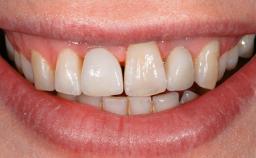

Repeated Acrylic Fractures on a Mandibular Fixed Full-arch Implant-supported Metal/Acrylic Prosthesis

A 77-year-old male patient was referred for the management of frequent and repeated acrylic fracture of his existing mandibular fixed full-arch implant-supported metal/acrylic prosthesis. He also complained about softtissue soreness and the lack of retention and stability of his maxillary removable partial metal/acrylic prosthesis. Both prostheses had been delivered two years previously as part of his full-mouth rehabilitation (caries, tooth wear, tooth fracture). His medical history revealed high blood pressure, controlled with the use of antihypertensive medication.